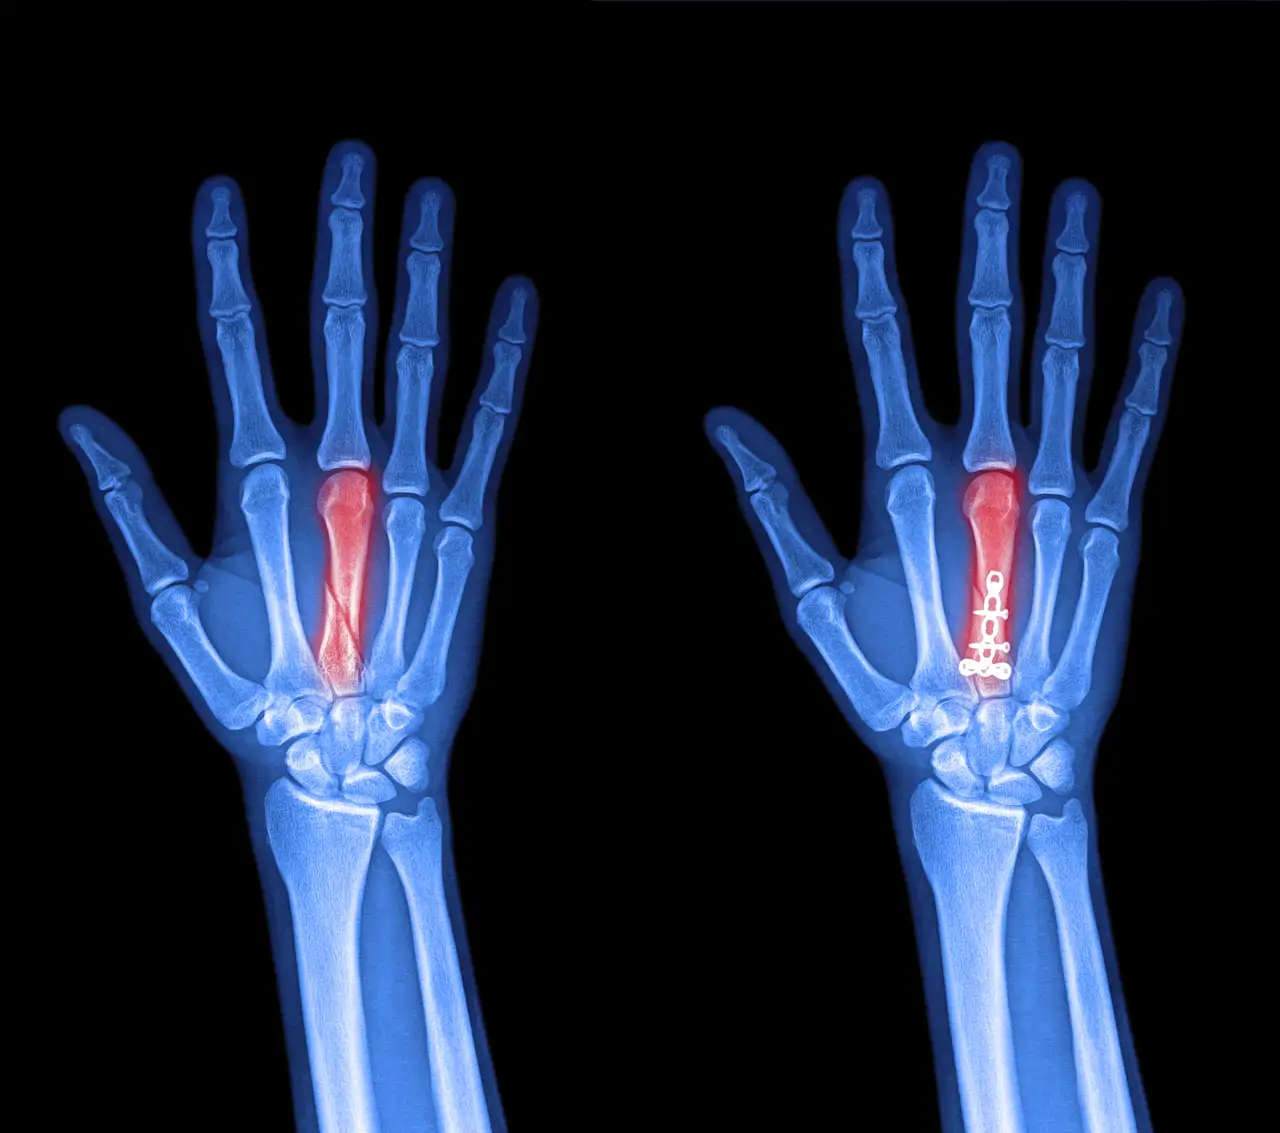

El índice-anular (2D:4D)

El cociente entre la longitud del segundo (índice) y el cuarto (anular) dedo se conoce como 2D:4D. En términos generales, un 2D:4D más bajo (con anular notablemente más largo) se asocia a mayor exposición androgénica prenatal y, según los estudios, este rasgo indicaría que el embrión estuvo expuesto a niveles relativamente altos de testosterona.